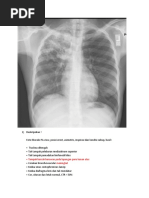

Contoh Expertise :

Jenis Foto : Thorax PA

Deskripsi : CTR < 50%

Tampak perselubungan homogen pada laterobasal paru kiri disertai garis ellis

Kesan : Effusi Pleura kiri